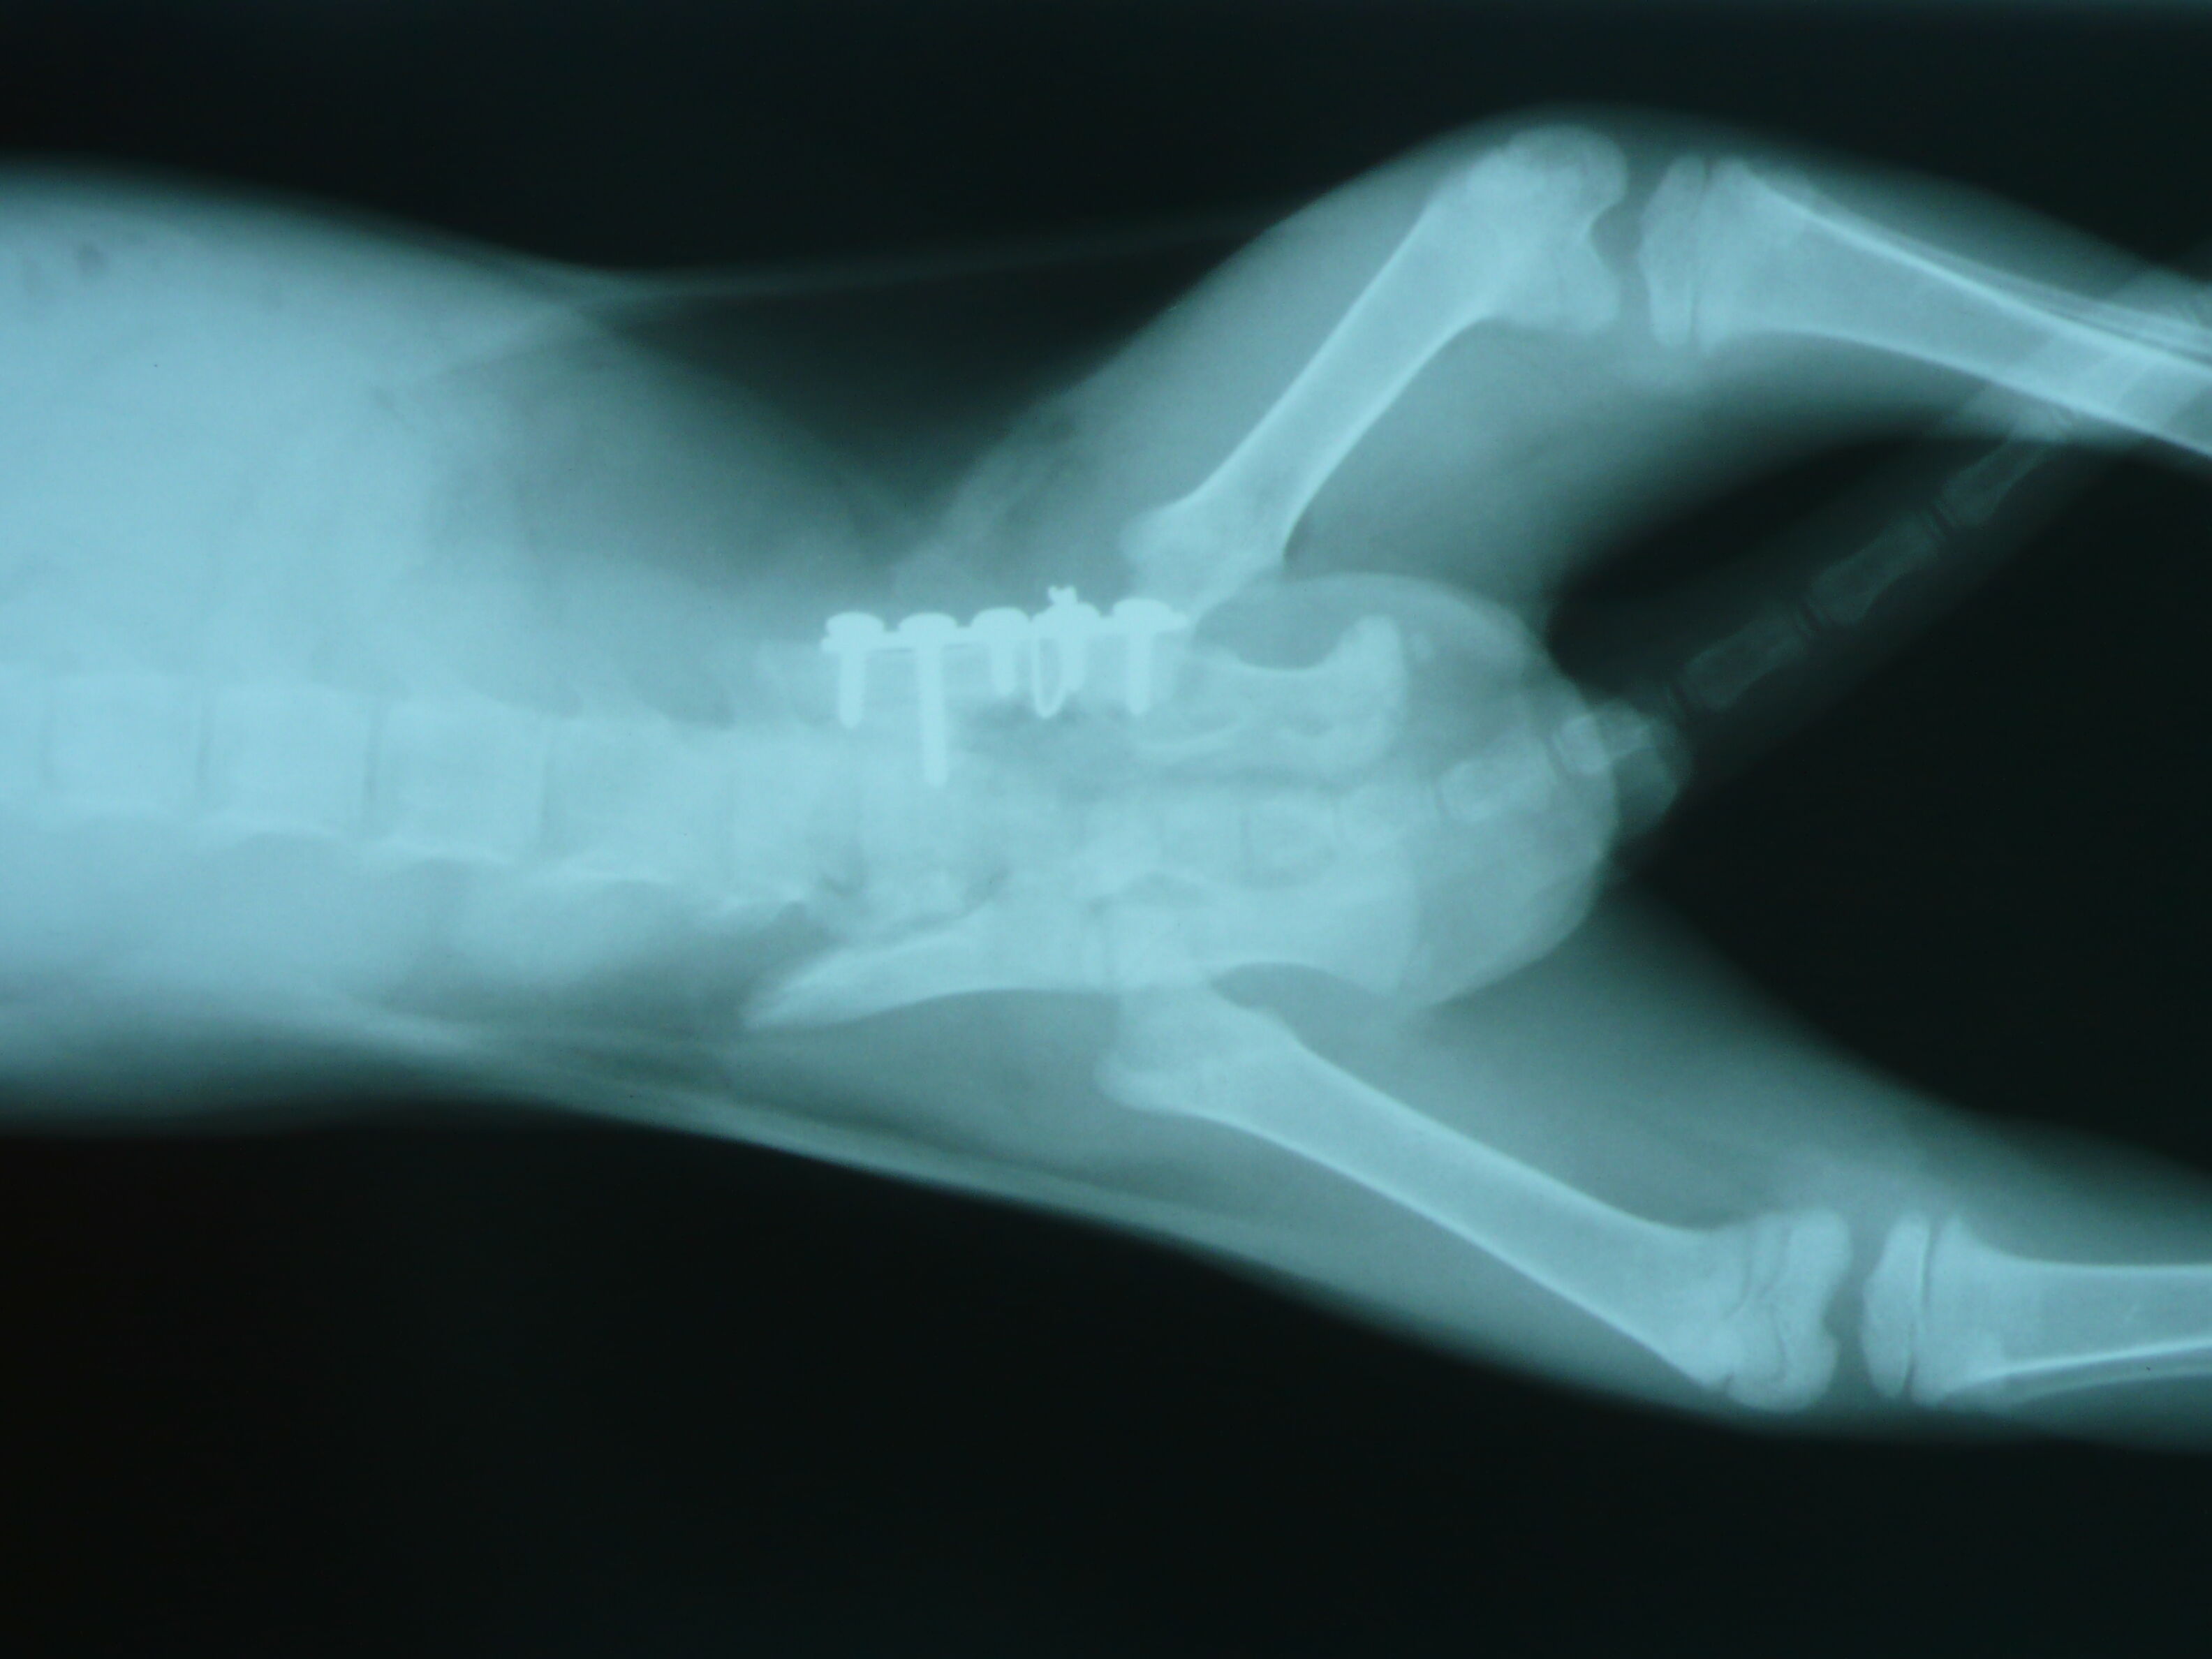

主題: 大同區大龍街骨盤骨折手術小橘白(手手) 申請者姓名: Akimasa Tu 花色: 申請日期: 2012-12-12 00:10:20 申請者部落格: 申請者臉書網址: https://www.facebook.com/akimasa.tu 所在縣市/合作醫院: 台北市/長沁動物醫院 治療費用: 38160元 需求人數: 40人 已結案 (2013-08-06 13:46:45) 報名人員: Hegel Tsai(已付款)、Annabel Wong(已付款)、Ivana Wang(已付款)、火鳳貍(已付款)、Bubujojo(已付款)、Joyce Lien(已付款)、謝佩芳(已付款)、Vincent Ho(已付款)、orangekitten、vanessa(已付款)、wei(已付款)、賴育辰、Minnie Lu(已付款)、劉小蕎、AMY(已付款)、芒果舜(已付款)、Mia Jheng(已付款)、Pa Ssion(已付款)、Pettie Chang、Moon Cat(已付款)、Candice Chao(已付款)、tombosan(已付款)、hungers(已付款)、楊挨打(已付款)、楊挨打、Hugo(已付款)、Jotaro Lin(已付款)、Alison Lee(已付款)、zoechengtw(已付款)、Katrina Chen(已付款)、Emma Chu(已付款)、不不熊(已付款)、Alumi Lu(已付款)、Joyce Hsu(已付款)、以四面佛名義迴向阿咪丶咪仔(已付款)、以四面佛名義迴向阿咪、咪仔(已付款)、Joyce Hsu(已付款)、以四面佛名義迴向阿咪丶咪仔(已付款)、以四面佛名義迴向阿咪丶咪仔(已付款)、以四面佛名義迴向阿咪丶咪仔(已付款)、陳大熊、Miss.Au(已付款)、Fan Chang x3(已付款)、Shirley Tsai(已付款)、 候補人員: 動物病情說明: 這隻小貓是在大龍街一間二手店外面,被一位在當地上班的志工發現,

似乎也無法自行排便,每次都蹲很久大不出來,照X光後才發現,這小

貓有嚴重的骨盤腔骨折,且已經開始癒合,導致無法順利排便,只能每

天用手擠出,且大便形狀是呈凹字形一整條狀,骨盤腔變形非常嚴重!

的說沒有幼貓可用的骨板,張醫師則說手術沒問題,生長板不會有影響

,可以改善排便,有其他的骨板可以使用,因為小貓擠大便很痛苦,每

之苦,聽醫師建議,決定用手術方式!